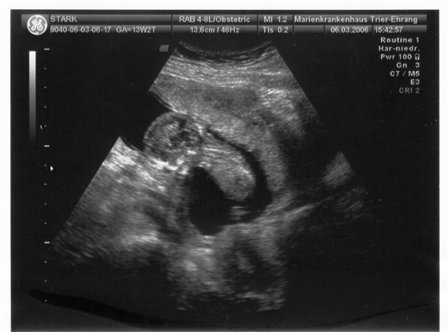

Die Beiden sind jetzt ordentlich gewachsen! Ich bin jetzt in der 13. Woche und sie sind 7,0 und 6,2 cm groß (Scheitel-Steißlänge). Freitag muss ich zum Feinultraschall zum Spezialisten (da wird dann auch Nackenfaltenmessung und Ersttrimesterscreening gemacht). Hoffentlich wird ausgeschlossen, dass eine Unter-/Überversorgung (wegen der gemeinsamen Plazenta) vorliegt. 8 mm Größenunterschied sollen ja noch normal sein, meinte meine FÄ, zumal das Kleinere etwas ungünstig lag ...

so wie es aussieht ist alles in ortnung also unser Baby ist gesund. Die Nackenfalte ist sehr klein :dance:. Unser Krümmel ist vom Kopf bis Popes knappe 7,5 cm groß und sieht echt süß aus. der Arzt war sehr Lieb und hat alles aber wirklich alles gezeigt. Er hat auch versucht zwischen den Beinchen zu gucken aber uns krümmel hat nix gezeigt :snooty:. aber egal. der Wurm hat sich bewegt ohne ende man konnte Beinchen;Ärmchen, Nase und Äuglein sehen und er saß in einer Hockstellung man konnte die einzeln Knochen am Knie sehen. Boah das war echt toll :dance:.